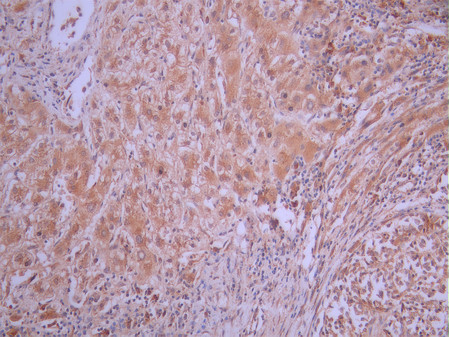

• IHC image of CSB-RA148565A0HU diluted at 1:100 and staining in paraffin-embedded human stomach tissue performed on a Leica BondTM system. After dewaxing and hydration, antigen retrieval was mediated by high pressure in a citrate buffer (pH 6.0). Section was blocked with 10% normal goat serum 30min at RT. Then primary antibody (1% BSA) was incubated at 4°C overnight. The primary is detected by a Goat anti-rabbit polymer IgG labeled by HRP and visualized using 0.05% DAB.

• IHC image of CSB-RA148565A0HU diluted at 1:100 and staining in paraffin-embedded human liver cancer performed on a Leica BondTM system. After dewaxing and hydration, antigen retrieval was mediated by high pressure in a citrate buffer (pH 6.0). Section was blocked with 10% normal goat serum 30min at RT. Then primary antibody (1% BSA) was incubated at 4°C overnight. The primary is detected by a Goat anti-rabbit polymer IgG labeled by HRP and visualized using 0.05% DAB.